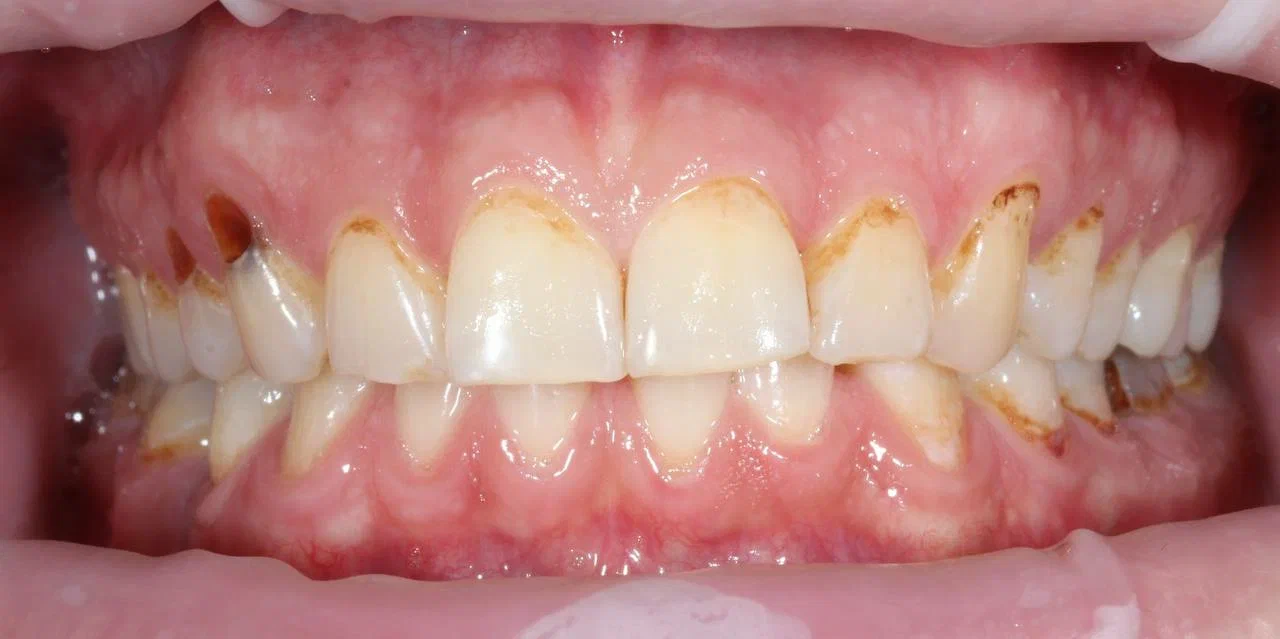

А так выглядит сигаретный налёт на зубах курильщика. Почувствуйте разницу.

Потемнение эмали. Это самый яркий, так сказать, бросающийся в глаза признак постоянного курения. В стоматологии для этого придумали даже специальный термин «никотиновые зубы». Характерный жёлтый цвет зубов плохо поддаётся профессиональной чистке, особенно, если личная гигиена у человека хромает и он редко посещает стоматолога. Этот тёмный налёт курильщика образуется в несколько стадий:

- Сначала из-за разницы температуры горячего (40–60ᵒС) сигаретного дыма и вдыхаемого воздуха на поверхности эмали образуются микротрещины, в которые проникают табачные смолы.

- Затем на поверхности зубов курящего образуется смоляная плёнка, под которой накапливается патогенная микрофлора, образующая зубной камень такого же тёмного цвета.

Локализация тёмного налёта у курильщика в пришеечной и межзубной зонах. Впоследствии именно здесь чаще всего образуется кариес — на фото его можно увидеть на правом верхнем клыке и левой нижней шестёрке.